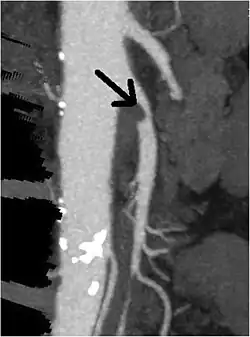

A computed tomography angiogram showing stenosis of the superior mesenteric artery (arrow).

Abdominal angina is diagnosed by identifying stenosis with imaging.[10] Since the symptoms of abdominal angina overlap with various other disorders, other causes of symptoms are ruled out as a part of the diagnostic process. Gastric ulcers, abdominal aortic aneurysms, and gastrointestinal cancers can have similar symptoms and can be ruled out by esophagogastroduodenoscopy, CT scans, or MR angiogram. Other differential diagnoses include GERD, dietary or food sensitivities, constipation, pancreatitis, abdominal abscess, appendicitis, irritable bowel syndrome, gastroenteritis, hepatitis, and inflammation of the gastrointestinal system.[11] Duplex ultrasound, MR angiography, angiography, and computed tomography angiography can be used to help confirm the diagnosis of abdominal angina.[3] Duplex ultrasound may be used to screen for abdominal angina but is not ideal for visualizing stenosis. Angiography, MR angiography, or CT angiography can be used to further visualize the celiac and mesenteric arteries.[12]